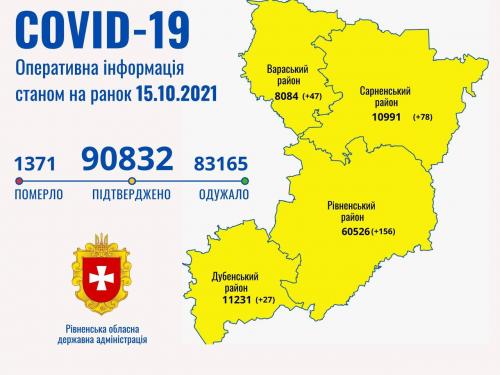

Коронавірус повертається: як стрімко зростає кількість хворих на Рівненщині (ВІДЕО)

Пів тисячі - у важкому стані, 9 жителів Рівненщини померли за добу від коронавірусу